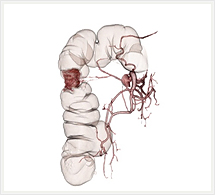

大腸

CTでは輪切り像の他にも立体的な画像(3D画像)を作成することもできます。そのためにはより細かくキレイな画像を撮影しなければなりません。当院では64列CTを導入しており、キレイな画像をより細かく撮影することができます。その画像を元に3D画像を作成することによって、より正確な手術のシミュレーションが可能になります。実際に手術をしたときの様子が、手術をする前に画像として見らます。外科系の手術には欠かせない技術となっておりますが、内科系でも血管内手術にも多く利用されております。

当診療放射線技術科では毎日各診療科に対して、その手術に最適な3D画像を提供しております。

以下にその3D画像を一部分紹介します。